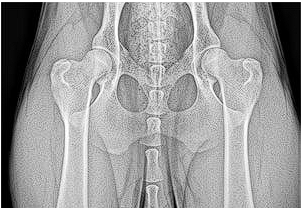

All breeding dogs undergo X-ray evaluation of their elbows and hips via Pennhip and OFA preliminary certification prior to 24 months. Any dogs not passing evaluation will not be bred.

Veterinary Evaluation of Patellar Luxation. Results registered with OFA.